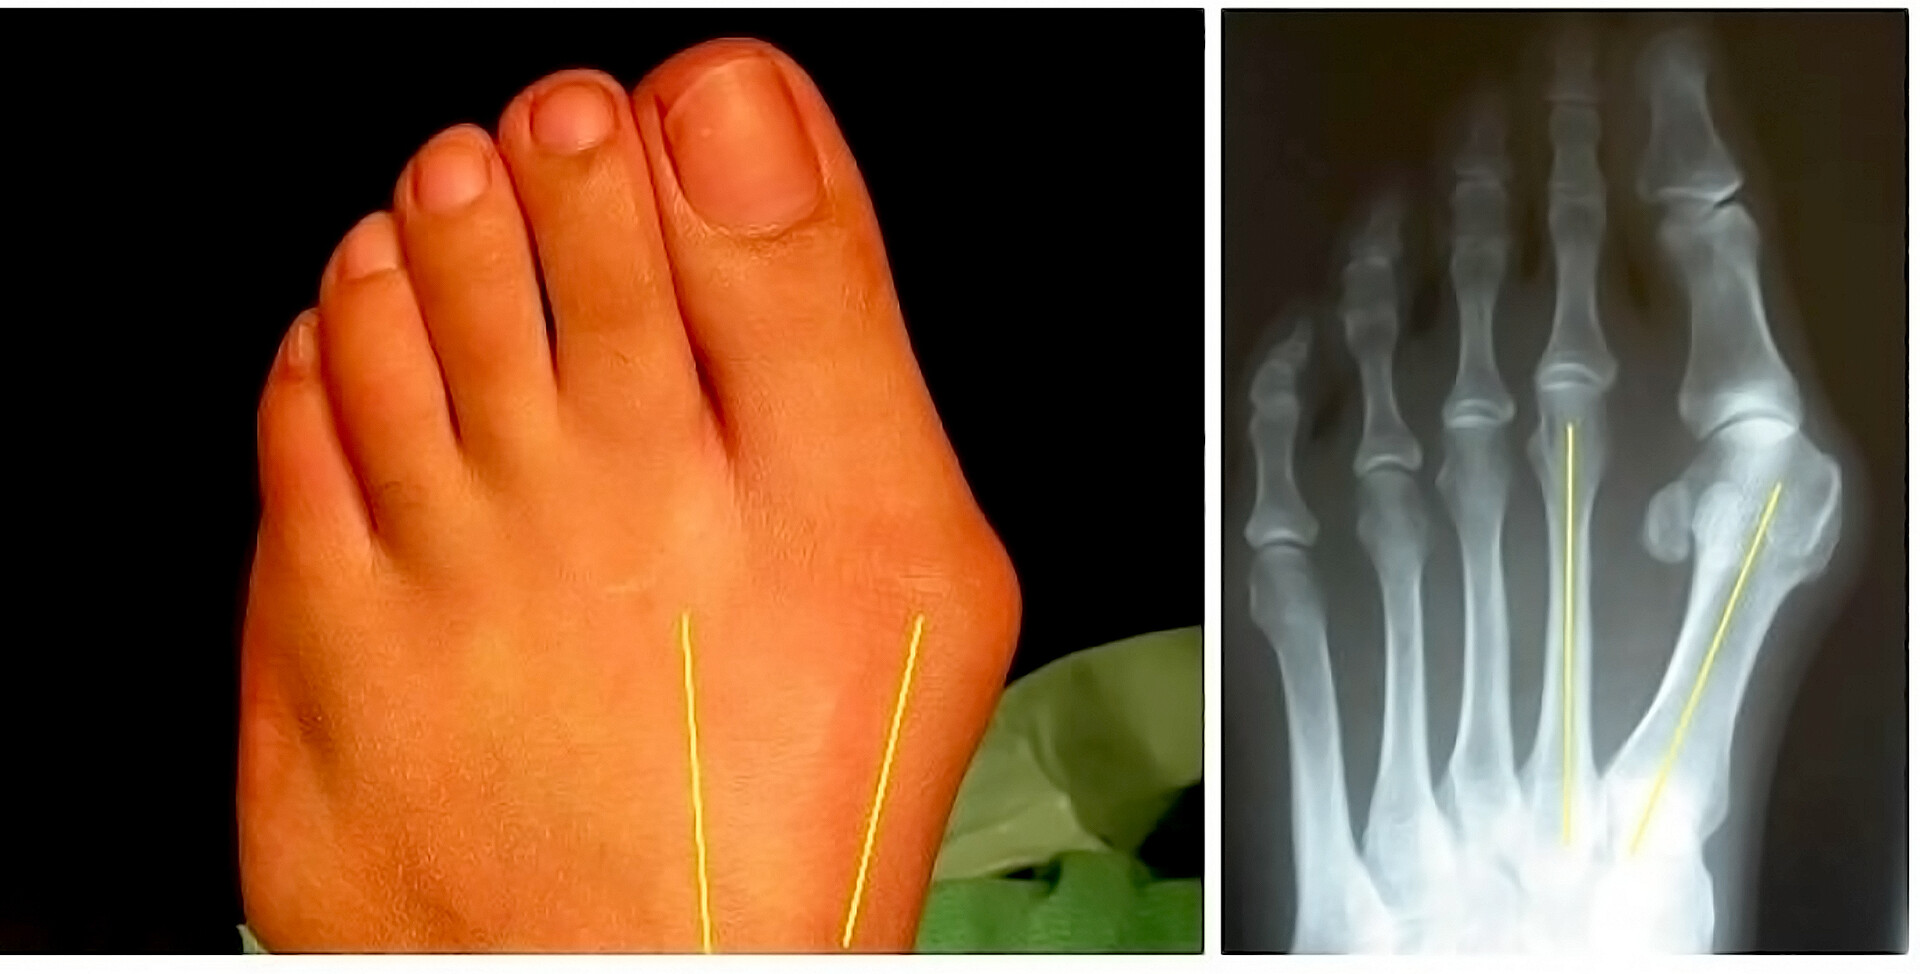

Экзостоз пальцев стопы

Экзостоз пальцев стопы 143 фотографий